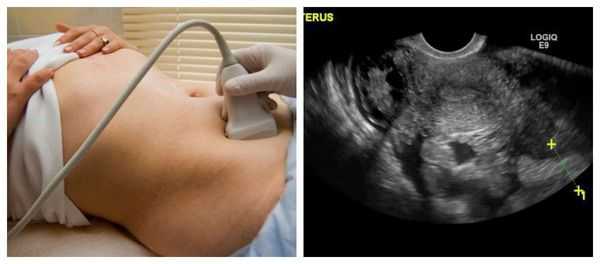

Точность в постановке правильного диагноза возможна лишь при помощи проведенного ультразвукового исследования (УЗИ) половых органов женщины. Врач - диагност, применяя специальный медицинский аппарат, внимательно осматривает органы малого таза, маточную полость, состояние эндометрия. УЗИ позволяет выявить оплодотворенное яйцо и место его закрепления.

Если при всех признаках беременности эмбрион в матке не обнаружен, при этом диагност наблюдает присутствие сгустков крови и жидкости в полости брюшины или в области за маткой, врач ставит диагноз - внематочная беременность.

Яичниковая беременность на УЗИ

Следует так же отметить, что может сложиться такая клиническая картина, когда тест показал две полоски, что соответствует положительному ответу на оплодотворение яйцеклетки, тогда как ультразвуковое исследование говорит обратное - эмбриона в матке нет. Данное несоответствие и является одним из указаний на развивающуюся внематочную беременность.

Поэтому исследование проводят более тщательно. Яичниковая беременность на узи определяется, если плодовое яйцо располагается в проекции яичника. При этом врач - диагност обычно наблюдает, что эмбрион с маткой непосредственно соединяются связкой яичника.